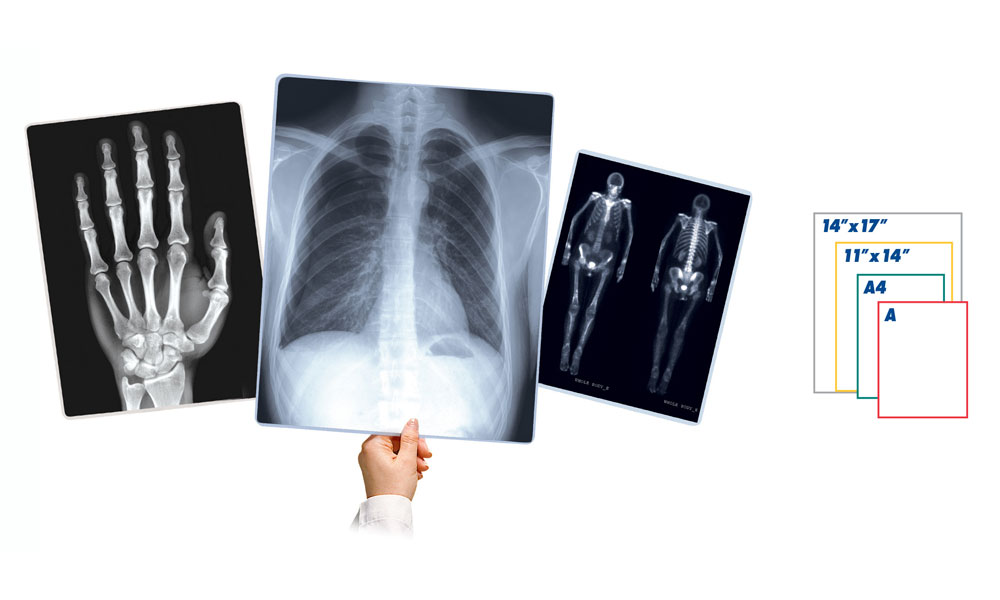

| Diagnostic Film | 14″x17″ 11″x14″ 8″x10″ |

| Grayscale Paper | 14″x17″ A A4 |

| Diagnostic Film | 14″x17″ 11″x14″ 8″x10″ |

| Grayscale Paper | 14″x17″ A A4 |

| Diagnostic Film | 14″x17″ 11″x14″ 8″x10″ |

| Grayscale Paper | 14″x17″ A A4 |

| Diagnostic Film | 14″x17″ 11″x14″ 8″x10″ 14″x36″ 14″x51″ |

| Grayscale Paper | 14″x17″ A A4 |

| Color Paper | A A4 |